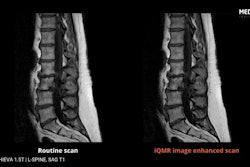

Given the unprecedented pace of AI development, it's vital to test AI integration into clinical workflows, U.S. researchers believe. Among other findings, they reported that biased AI model predictions with explanations lowered accuracy by as much as 9%.